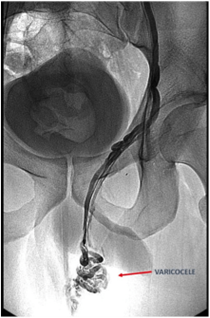

El pacient ha d’anar en dejú a la sala de Radiologia Vascular, que és un quiròfan equipat amb un angiógraf, dispositiu que, mitjançant l’ús de raigs X, permet navegar de manera controlada per dins dels vasos i conductes del cos. El radiòleg farà la punció d’una vena del braç per on entraran els catèters, navegarà amb el catèter fins al varicocele i realitzarà l’embolització del varicocele.

Embolització del varicocele

Que el tractament sigui incomplet o que el varicocele reaparegui pot passar en un 12-15% dels casos. Això s’explica, en part, per les diferències anatòmiques entre els pacients que se sotmeten al tractament, així com per l’existència de venes col·laterals que poden provocar que aquestes varius es recanalitzin malgrat haver rebut tractament previ.